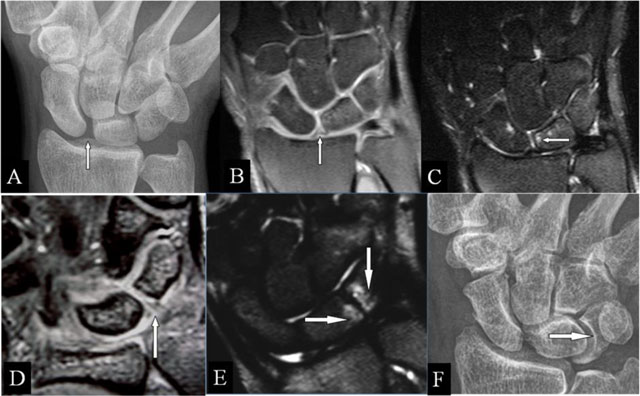

Figure 8

Scapholunar and lunotriquetral abutment. (A) PA plain radiograph; (B) Coronal SE PD-WI FS; (C) Coronal SE T2-WI FS; (D) Coronal 2D-GRE; (E) Coronal SE T2-WI FS; and (F) PA plain radiograph. (A) Widening of the scapholunate joint space on a Schneck I view. (B) Tear of the scapholunate ligament. (C) Juxta-articular subchondral band shaped marrow oedema. (D) Tear of the lunotriquetral ligament. (E) Juxta-articular band shaped kissing marrow oedema. (F) Massive deformation at the triquetral bone (other patient).